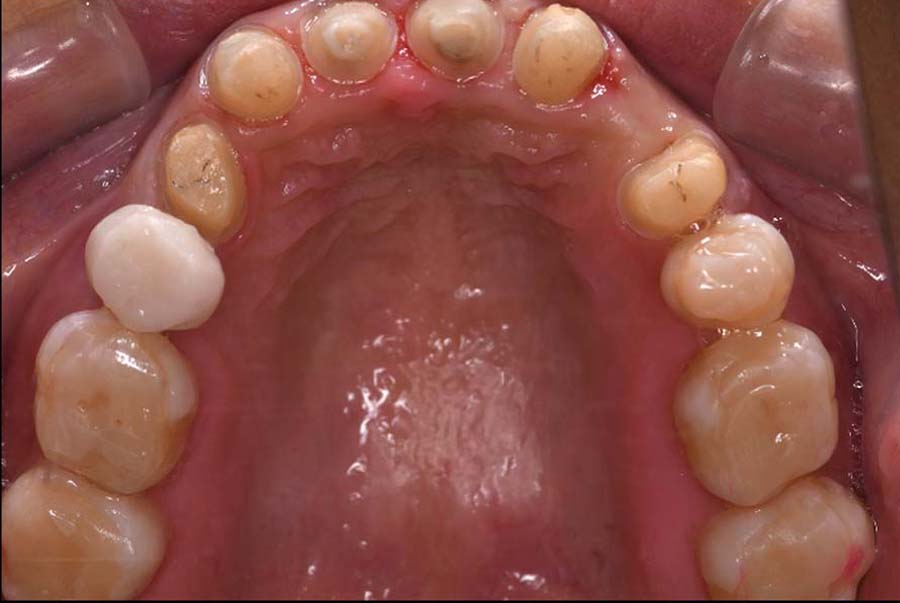

| 治療内容 | ①スプリントを装着 ②副子を装着 ③2024年4月 口腔内反映開始 ④副子を入れた状態の所まで咬合を挙上 (バイトアップ) ⑤2024年5月 上顎前歯部8本に仮歯(TEK) を装着 |

バイトアップ後